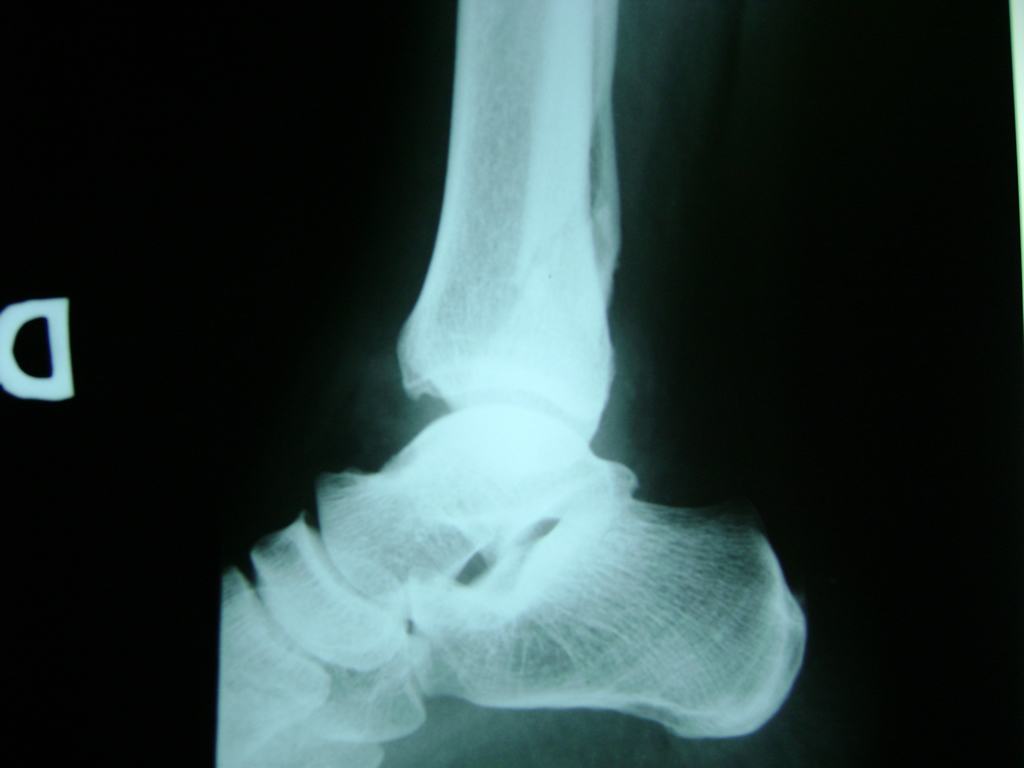

Algunas fracturas de tobillo pueden requerir cirugía si:

- Los extremos de los huesos están desalineados entre sí (desplazados).

- La fractura se extiende hasta la articulación del tobillo (fractura intra-articular).

- Los tendones o ligamentos (tejidos que sujetan los músculos y los huesos entre sí) están rotos.